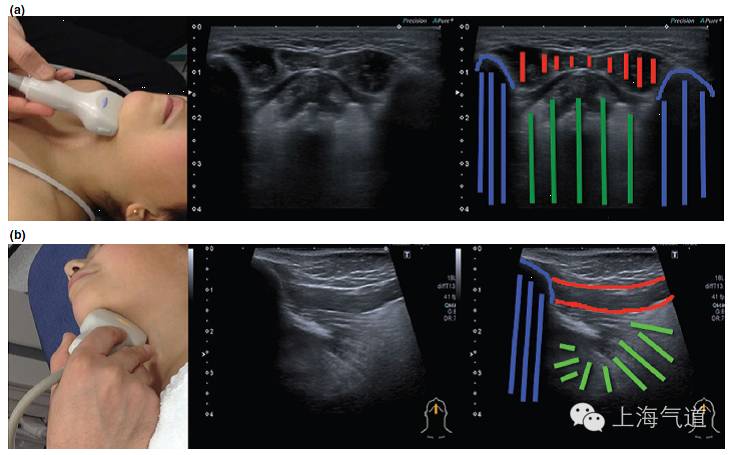

图3 a. 探头置于下颌骨水平取纵断面,黄色为颌下腺,红色为颈外动脉,棕色为扁桃体。b. 将探头旋转90度所得此区域的影像